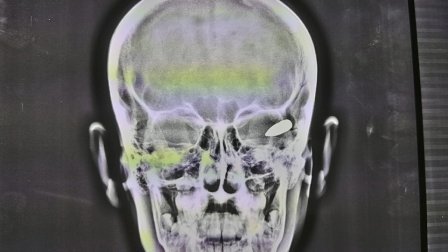

وأوضح أنه "بعد إجراء الفحوصات السريرية والإشعاعية تبين أن الرصاصة اخترقت عمق الدماغ ماتسببت له بشلل".

وتابع أنه تم "إجراء عملية معقدة لإخراج الرصاصة وتكللت بالنجاح"، مشيرا إلى أن "العملية أجريت بمساعدة فريق طبي مكون من د. مكرم نور الدين و د. اوفى اكثم و اخصائي التخدير د. احمد علي محروس ومساعد مخدر علاء حسين والممرضة فردوس ناظم والفيزياوي احمد علي".